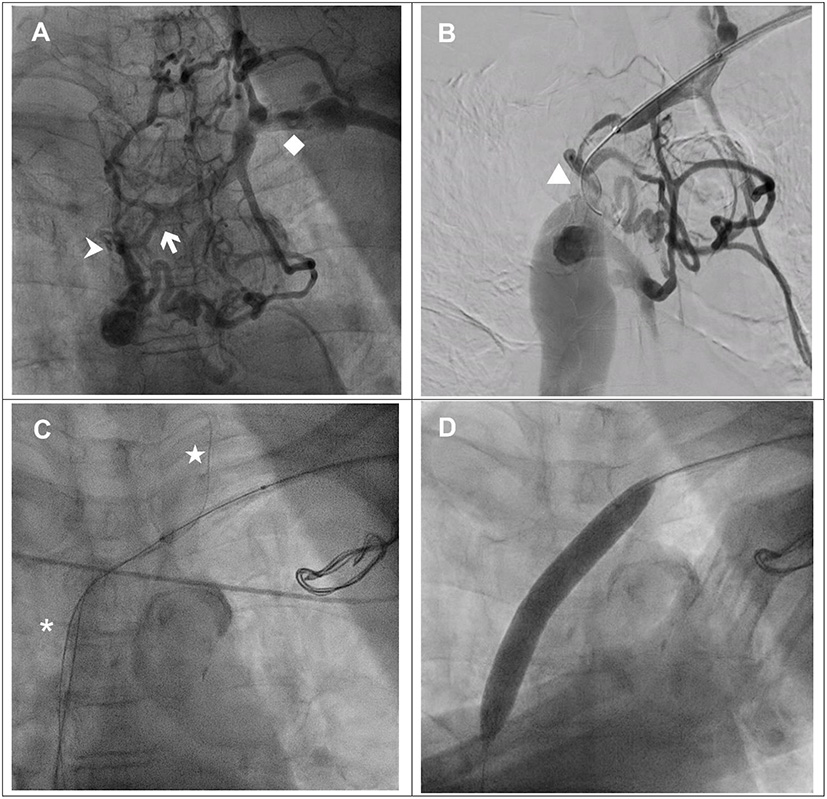

Figure 2. (A) The angiogram showed a patent brachiocephalic vein and superior vena cava after balloon venoplasty. (B) Implantation of right atrial, right ventricular and left ventricular leads.

Subsequently, the coronary sinus was cannulated, and a passive fixation LV lead (Medtronic 4598–88 cm) was implanted in the lateral vein with the parameters of R wave 0.6 mV, impedance 652 ohm, threshold 0.8 V @ 0.5 ms and 93.3% biventricular pacing. An active fixation lead in the right ventricle (Medtronic 5076–58 cm), an active fixation lead in the right atrium (Medtronic 5076–52 cm) and a generator (Medtronic Percepta™) with DDDR mode were implanted smoothly (Figure 2B). The total procedural time was 152 min, and the fluoroscopy time was 16 min. Postprocedural chest X-ray revealed no pneumothorax. The 12-lead ECG after CRT implantation showed a narrower QRS of 150 ms with biventricular paced rhythm.